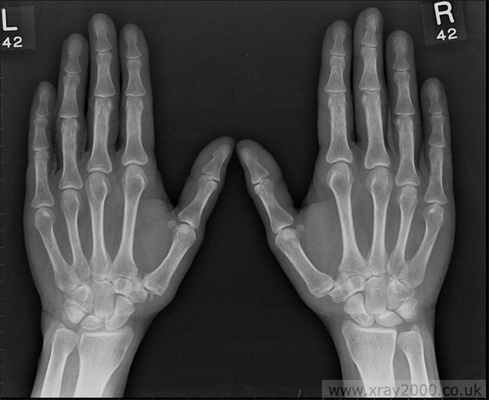

Характерным признаком заболевания при вовлечении суставов кисти является появление узелков Гебердена и Бушара, которые располагаются по краям межфаланговых проксимальных и дистальных суставов соответственно.

Остеоартроз мелких суставов кисти

Характеризуется следующими клиническими признаками:

- Наличие плотных узелков на боковых поверхностях дистальных межфаланговых суставов (узелки Гебердена) и на тыльно-боковой поверхности проксимальных межфаланговых суставов (узелки Бушара); Образование узелков сопровождается жжением, покалыванием, онемением (после завершения формирования узелков эти симптомы исчезают)

- Боль и некоторая скованность в суставах кисти, уменьшение объема движений.

- Прогностически наличие узелков Гебердена или Бушара является неблагоприятным признаком течения остеоартроза. (эта форма остеоартроза имеет генетическую детерминированность и передается по женской линии).